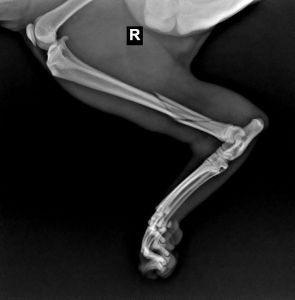

Na RTG vidíte frakturu s mírně dislokovaným úlomkem ‒ vážně si myslíte, že toto nebolí, nebo snad bolí méně než nás? Toto je reálný obrázek z naší praxe. Ortopedii neděláme, proto byla s majitelem dohodnuta operace na našem referenčním pracovišti. RTG jsme majiteli přeposlali na e-mail, stejně jako kolegovi na referenční pracoviště.

Výsledek? Majitel snímky konzultoval s jiným veterinářem a bylo mu sděleno, že operace není nutná. Ať kocoura zavře do malého prostoru a ono se to „nějak“ zhojí samo. Pokud je to pravda, promiňte, rád bych kolegu viděl fungovat se zlomenou nohou bez fixace!